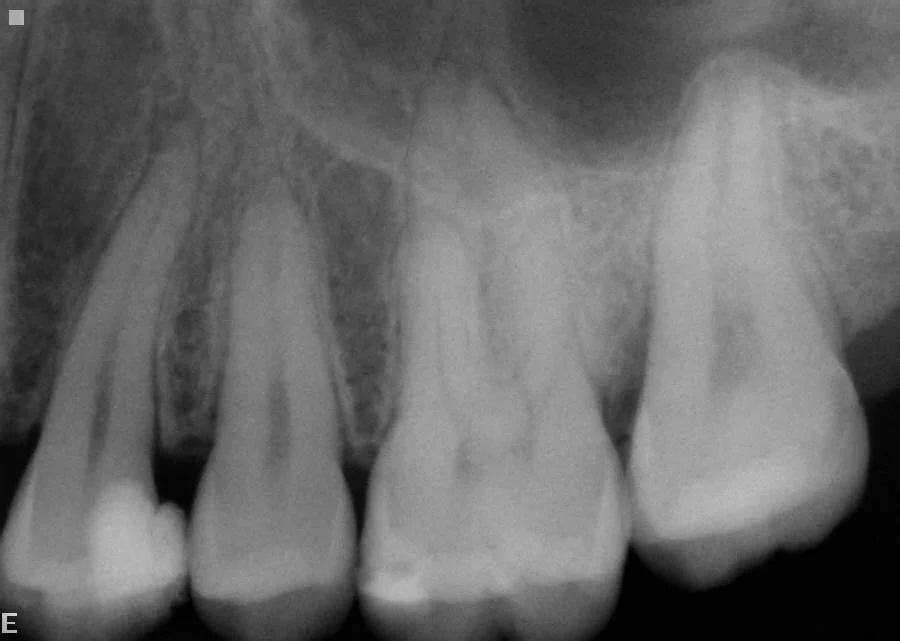

A lower molar has been extracted years ago and not replaced—leading to extensive over-eruption and tilting of the remaining teeth. This opens up contact points leading to food packing, decay, irregular bite and loss of further teeth. Always replace missing lower molars as soon as possible.